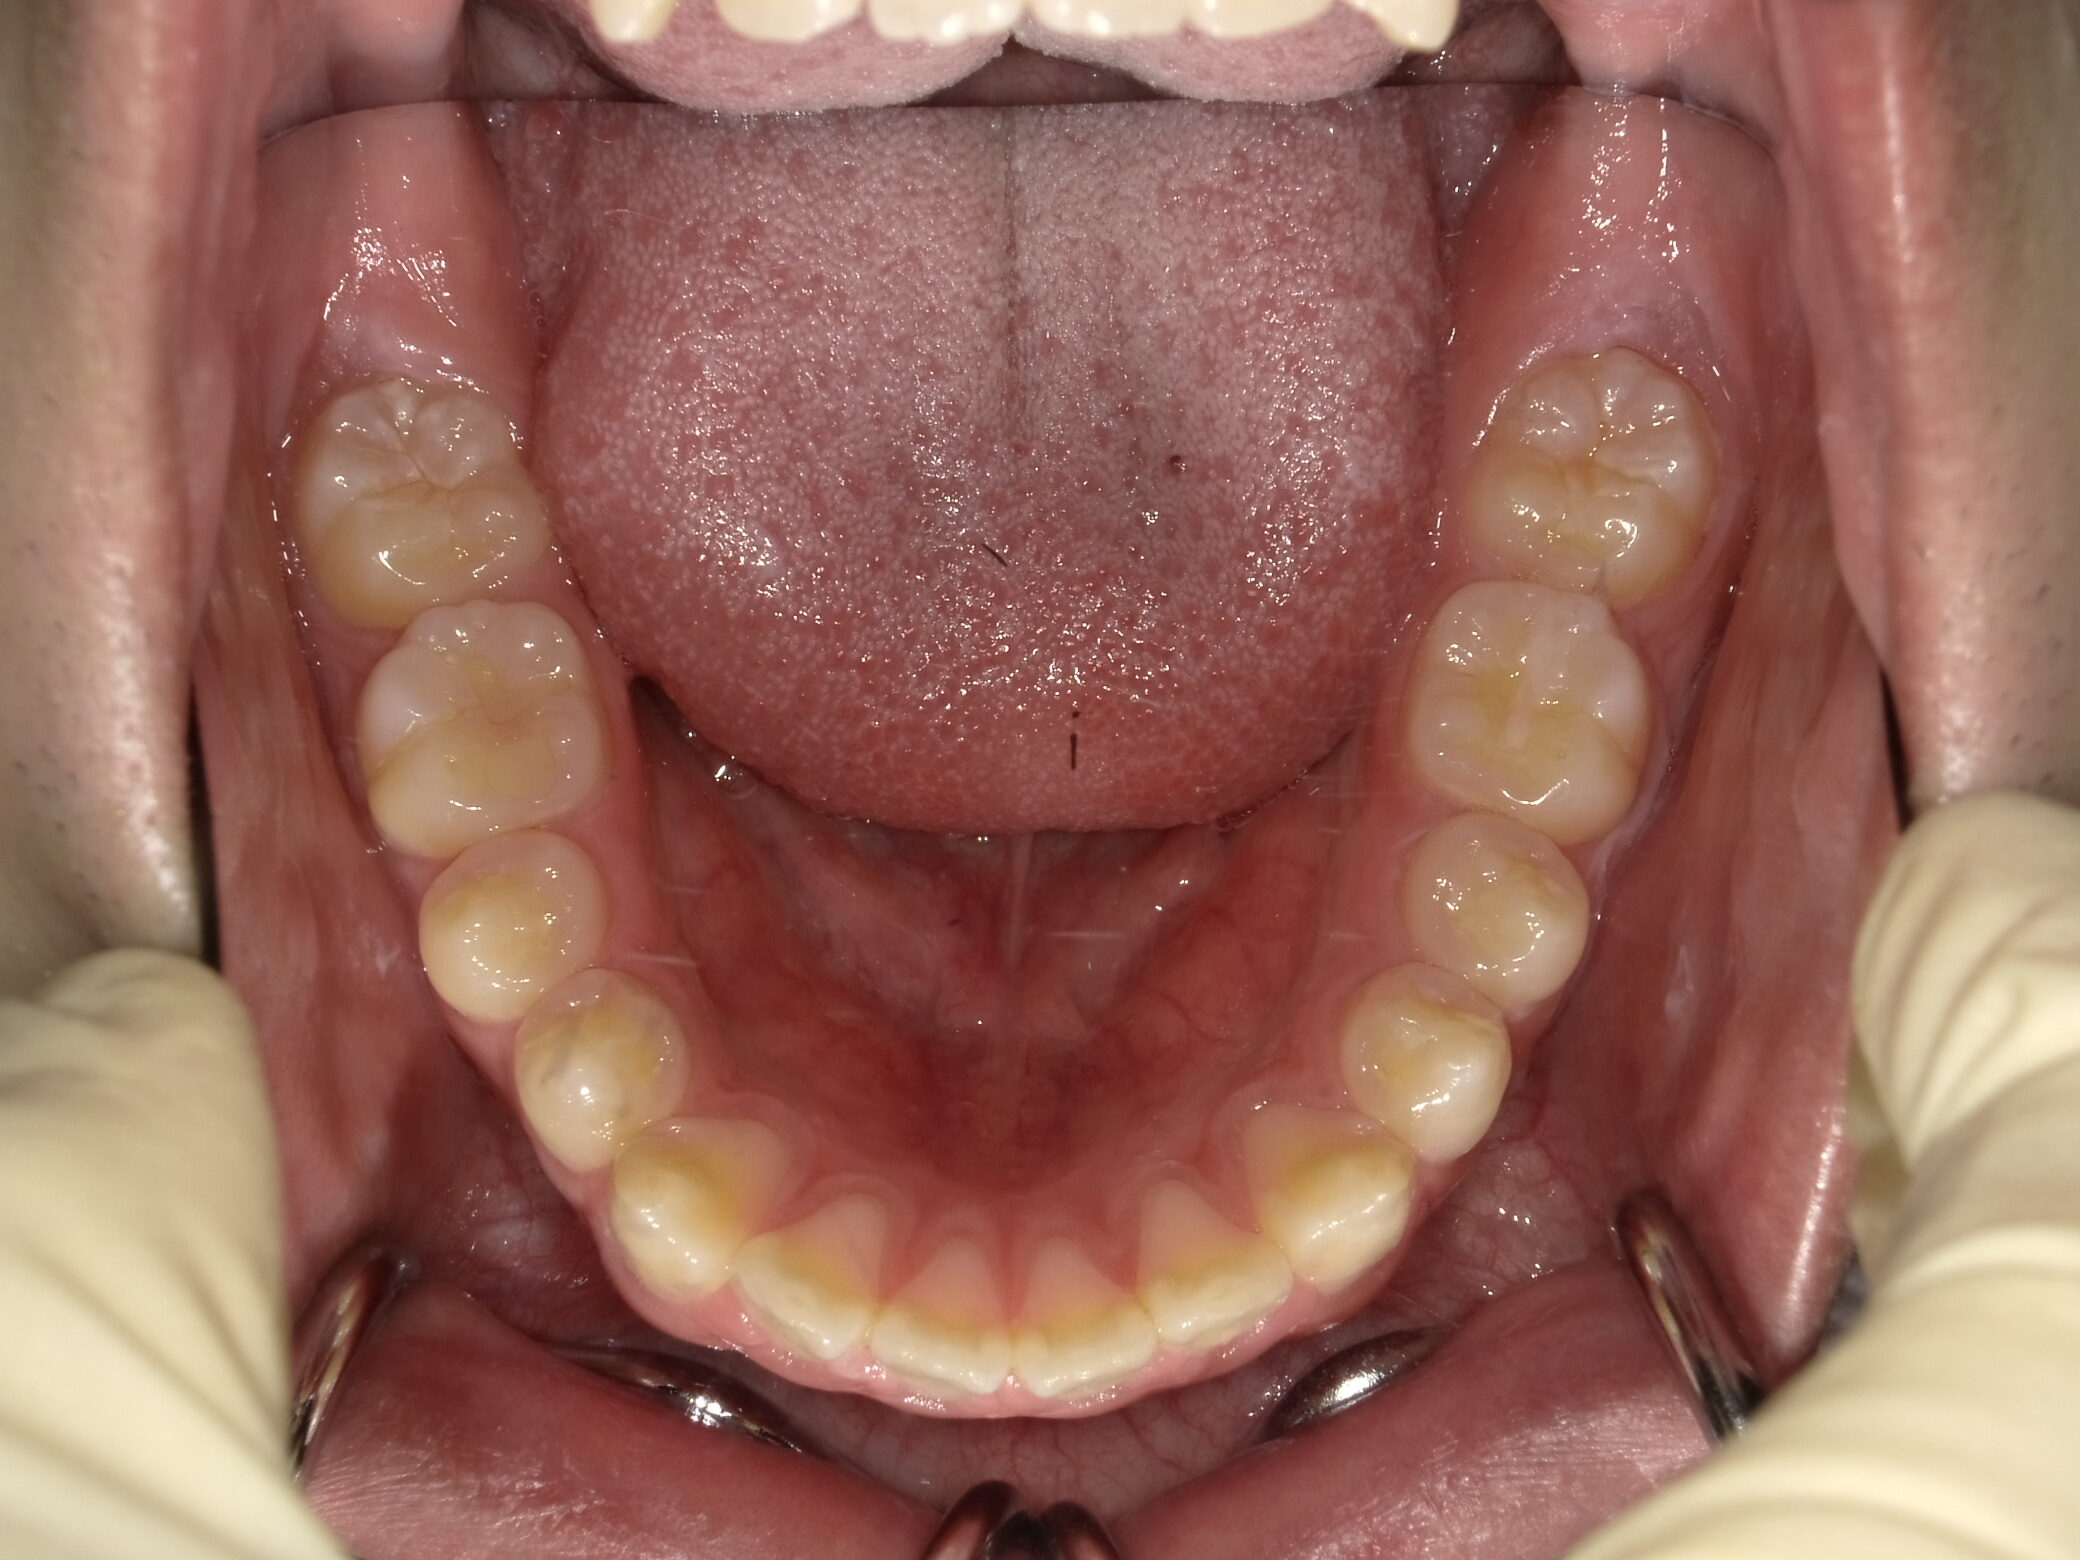

| 症例分類 | 上下顎前突 |

|---|---|

| 主訴 | 前歯が出ていて、口が閉じにくい |

| 年齢 | 20歳0ヶ月 |

| 性別 | 男性 |

| 抜歯部位 | 上下顎両側第一小臼歯 |

| 使用装置 | 歯の表側からのマルチブラケットによる矯正装置 |

| 治療期間 | 2年10ヶ月 |

| 保定装置 | 取り外し式保定装置 |

| 費用 | 相談料0円、検査料55,000円 動的矯正治療費935,000円 調整料6,600円×28回分 保定装置料0円 |

| リスク・注意点 | 上下の個々の歯の大きさに対して上下の顎が小さく歯が並ぶスペースが不足したために上下の前歯が前方に傾斜して、上下顎前突が生じています。これらを改善するために、上下顎両側第一小臼歯を抜歯して、このスペースを用いて歯を排列しました。歯の動き方には個人差があり、予想された治療期間が延長する可能性があります。 治療中は矯正歯科装置が歯の表面に付いており、歯が磨きにくくなるため、むし歯や歯周病が生じるリスクが高まります。ハミガキを適切に行ってお口の中を常に清潔に保ち、さらに、かかりつけ歯科医に定期的に受診することが大切です。 顎間ゴムの使用状況、定期的な通院など、矯正歯科治療には患者さんの協力が必要であり、それらが治療結果や治療期間に影響します。 治療の経過によっては当初予定していた治療計画を変更する可能性があります。 歯を動かすことにより歯根が吸収することがあります。 保定装置の装着時間が十分確保できない場合、歯並びや、咬み合せの「後戻り」が生じる可能性があります。 |